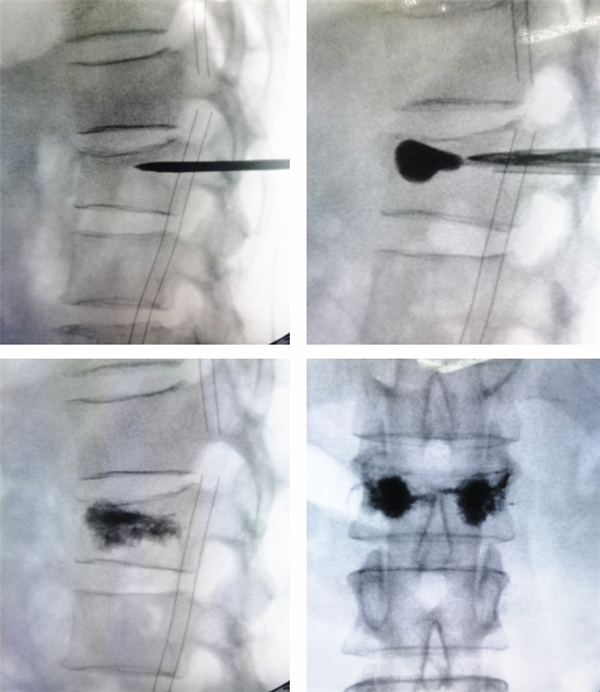

椎体成形术指经皮向骨折椎体注入骨水泥,以增加椎体强度,恢复椎体稳定,同时通过骨水泥发热来破坏痛觉神经,迅速止痛的一种微创脊柱外科手术。其优势如下:1.手术时间短,半小时左右即可完成。2.局麻操作,减少麻醉风险。3.X线透视定位,精准安全操作。4.微创操作,切口仅1cm左右。5.即刻缓解疼痛,术后即可下床。

入院后完善检查,排除手术禁忌后,由曹主任主刀,为王阿姨行“腰1椎体新鲜压缩骨折椎体成形术”。

椎体成形术微创治疗胸腰椎压缩性骨折